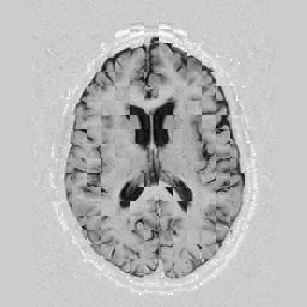

I later attempted 10 iterations at level 2, then 2 iterations at level 1, and 1 iteration at the finest level. Visual results can be seen in Figure [*].

Figure: Multi-scale NRR. From left to right, top then bottom: before NRR; after 10 iterations of NRR at level 2; after another 2 iterations of NRR at level 1; after 1 iteration at level 0.